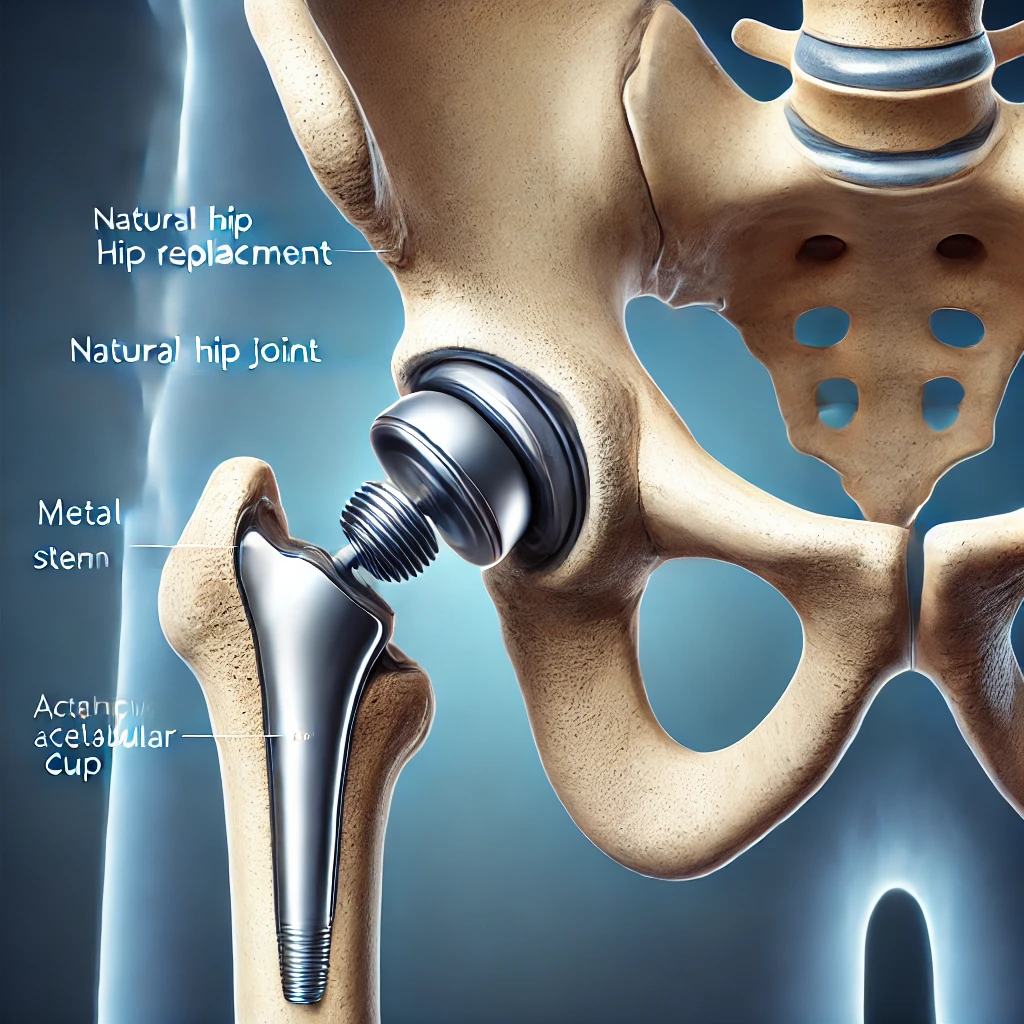

Τι είναι η Ολική Αρθροπλαστική Ισχίου;

Η ολική αρθροπλαστική ισχίου αποτελεί μια χειρουργική επέμβαση κατά την οποία ο φθαρμένος χόνδρος και τα οστά του ισχίου αφαιρούνται και αντικαθίστανται από τεχνητά εμφυτεύματα. Αυτή η διαδικασία αποκαθιστά την κίνηση της άρθρωσης και ανακουφίζει από τον χρόνιο πόνο.

Η Διαδικασία της Επέμβασης

Ο Νικόλαος Ζερβάκης εφαρμόζει εξελιγμένες τεχνικές ελάχιστης επεμβατικότητας που ελαχιστοποιούν τον χειρουργικό τραυματισμό. Η διαδικασία περιλαμβάνει:

- Αφαίρεση του κατεστραμμένου χόνδρου και οστών.

- Τοποθέτηση τεχνητού εμφυτεύματος (μεταλλικό ή κεραμικό).

- Εξισορρόπηση των μυών και των συνδέσμων για φυσική κίνηση.